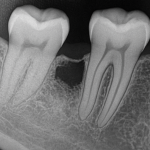

Ostateczną decyzję o ekstrakcji podejmuje lekarz po dokładnej ocenie i wykonaniu niezbędnych badań, takich jak zdjęcie rentgenowskie.